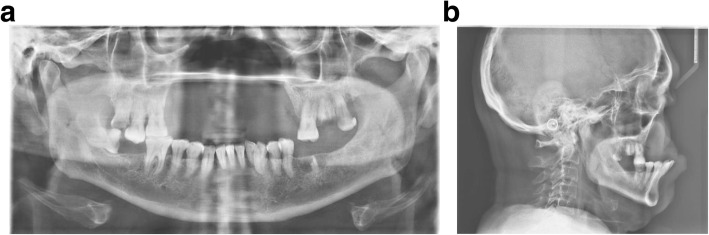

Fig. 3.

a Pre-operative OPG. All the upper incisors up to premolars missing bilaterally, as well as lower left molars. b Pre-operative laterocephalogram

Cephalometric analysis and computer tomography were performed (Fig. 3a and b) to evaluate the facial profile and to look for possibilities for anterior implant anchorage in order to achieve a respectful facial profile, most favorable loading conditions, and functionality of the future prosthesis.